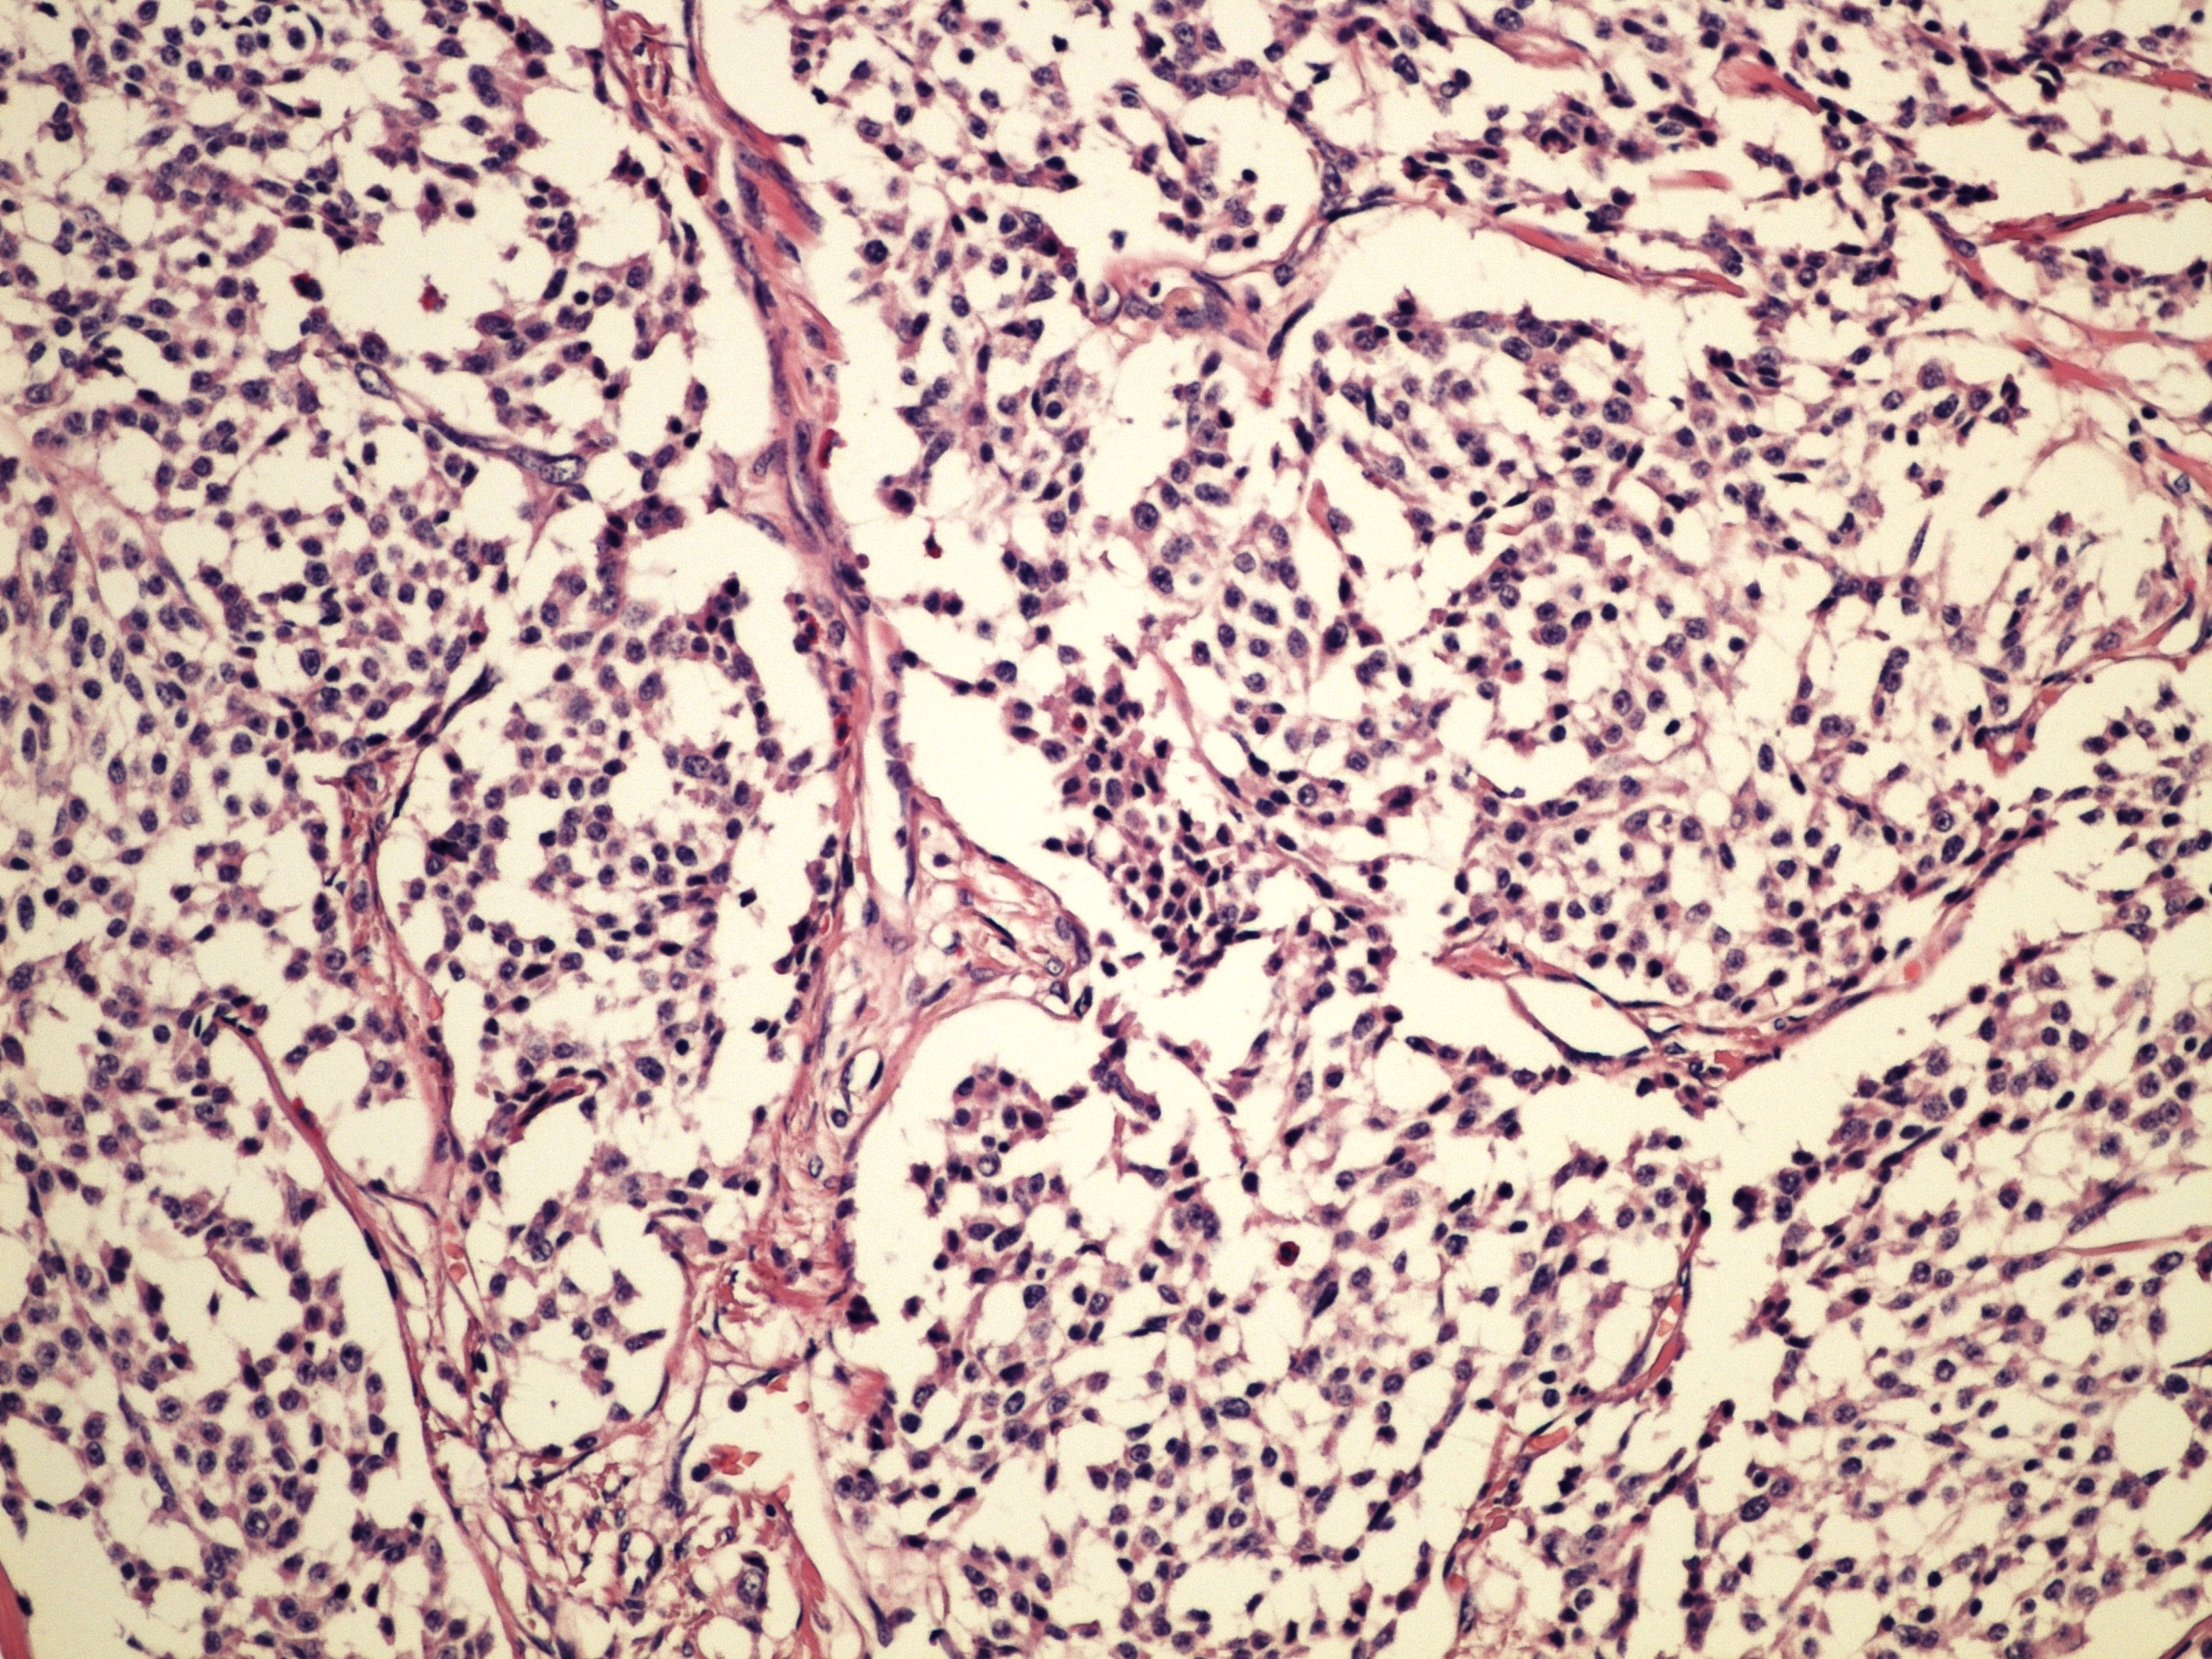

Preparát č.3 a č.4 – neuroendokrinní tumor

Struktury

- nádor

- stroma